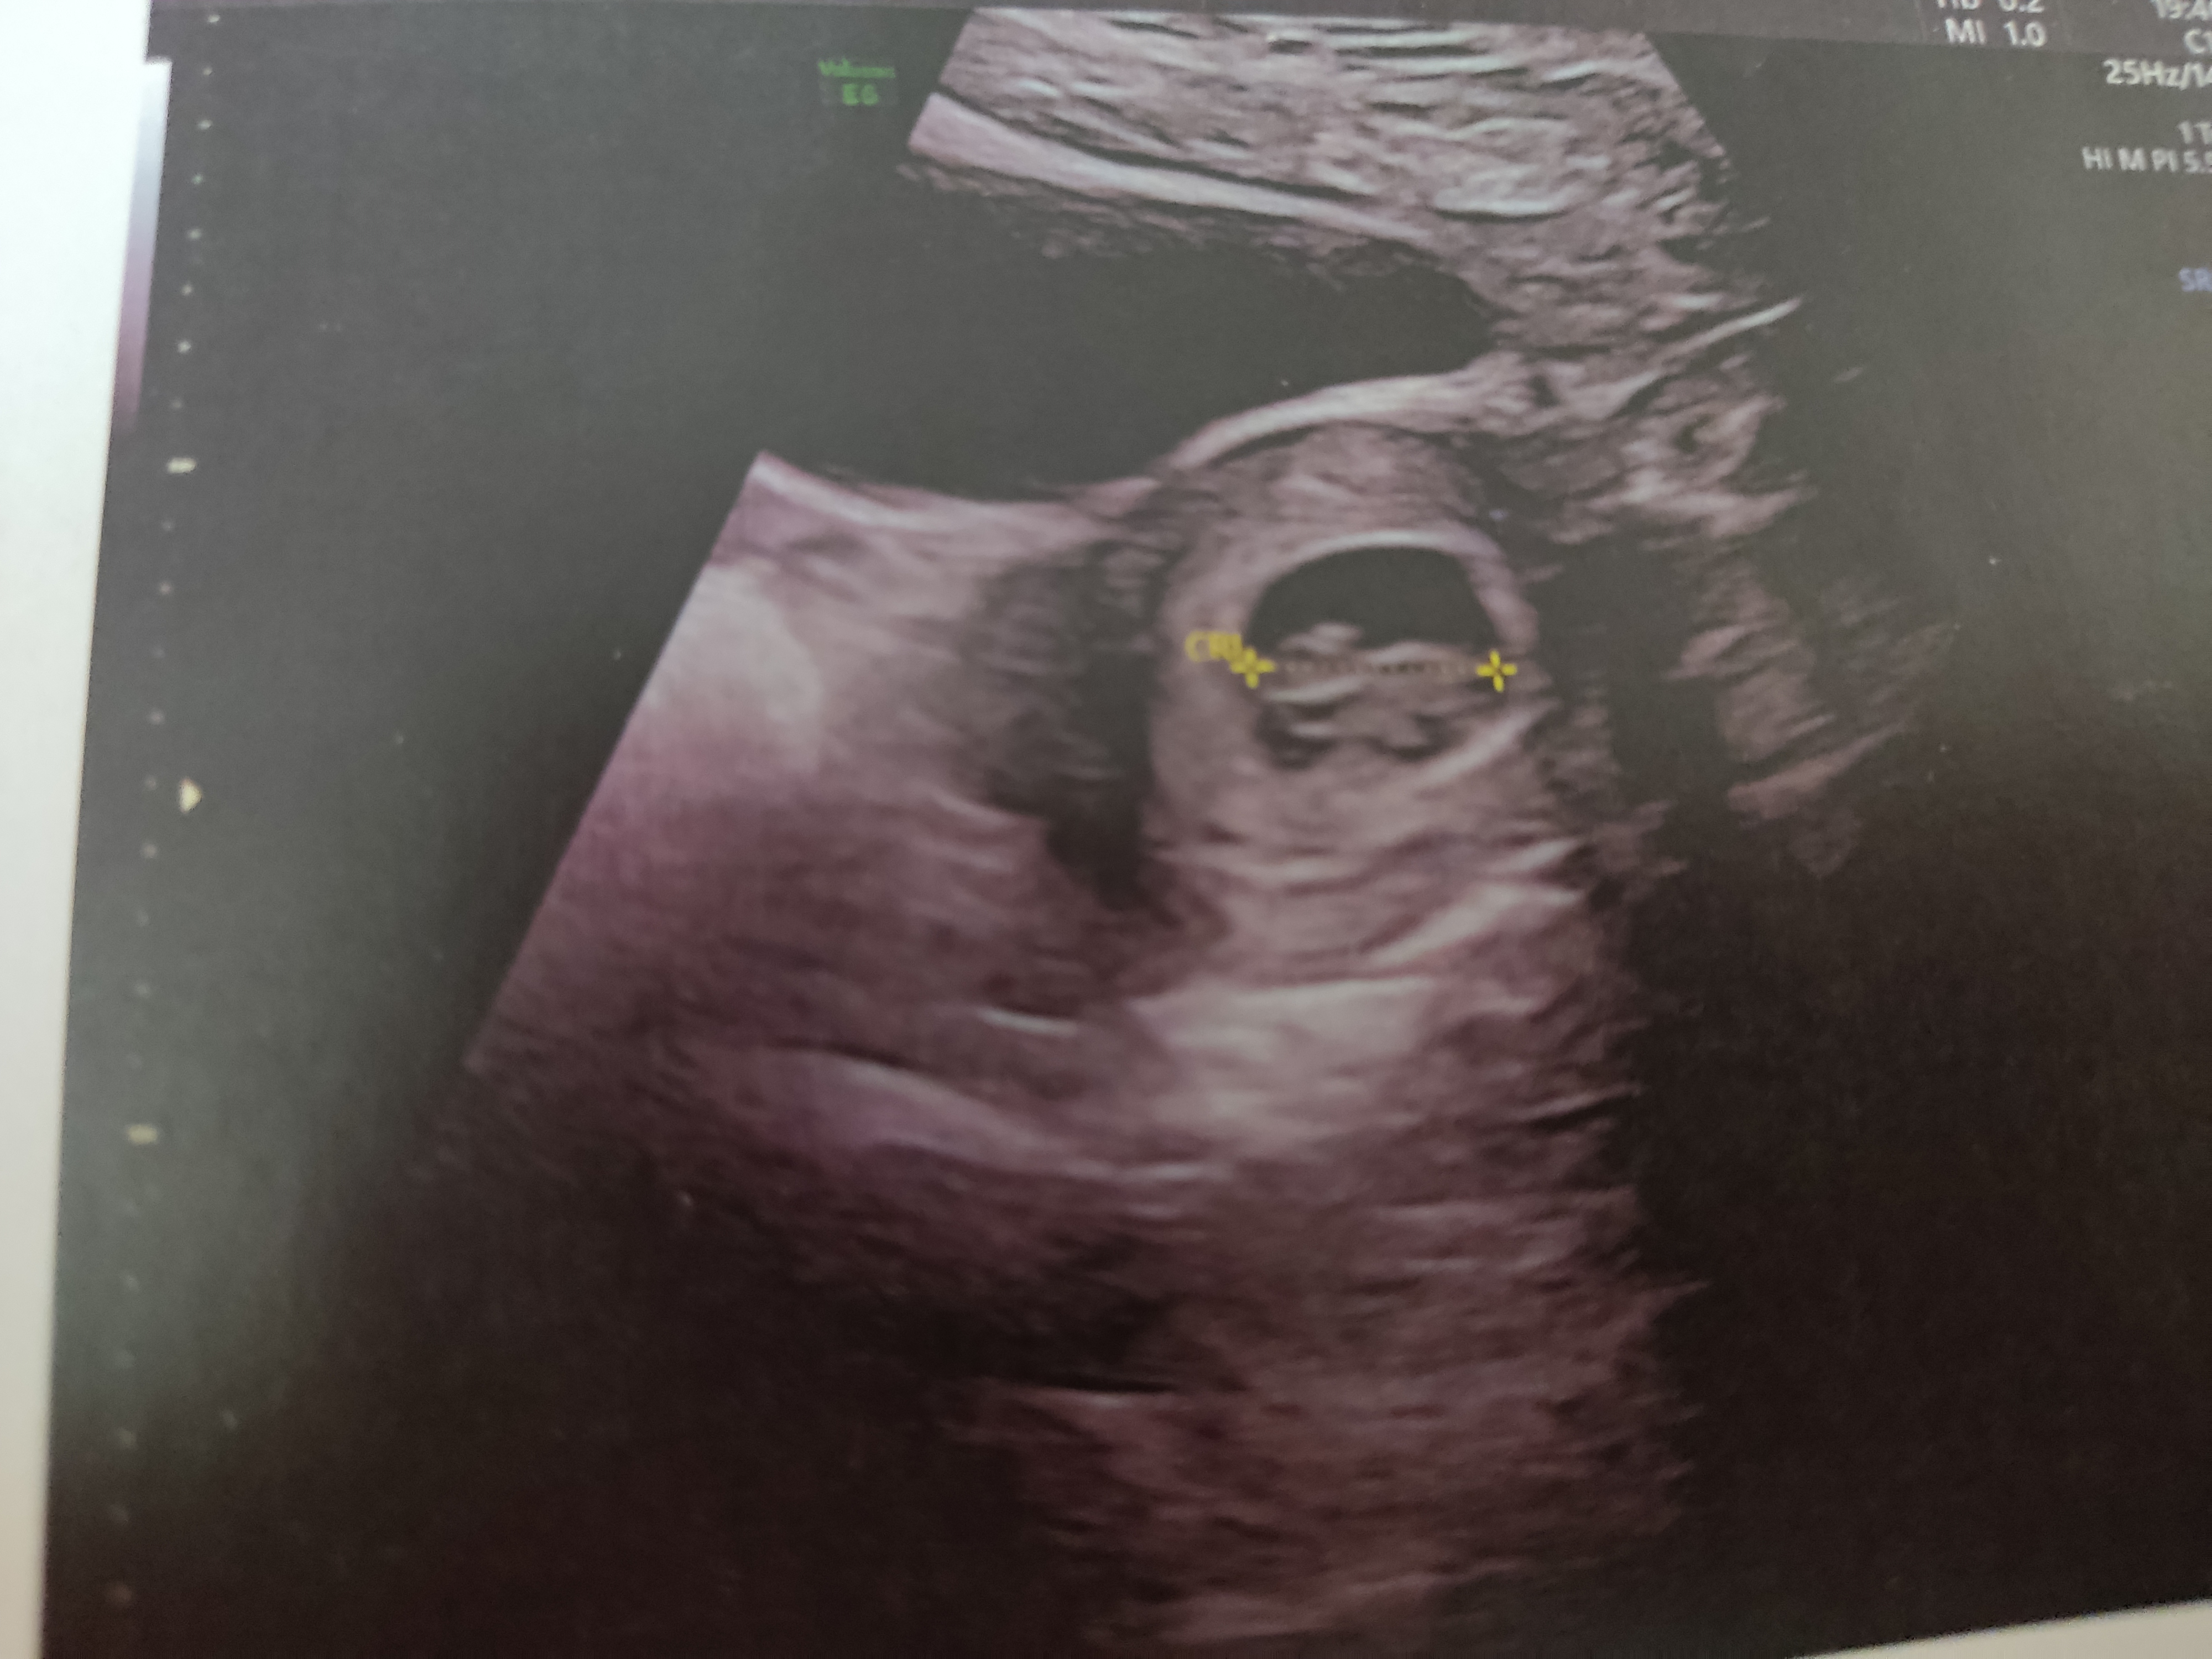

نمیدونماااا نمیدونماا ولی حس کردم دخترهههه😁🙌💓